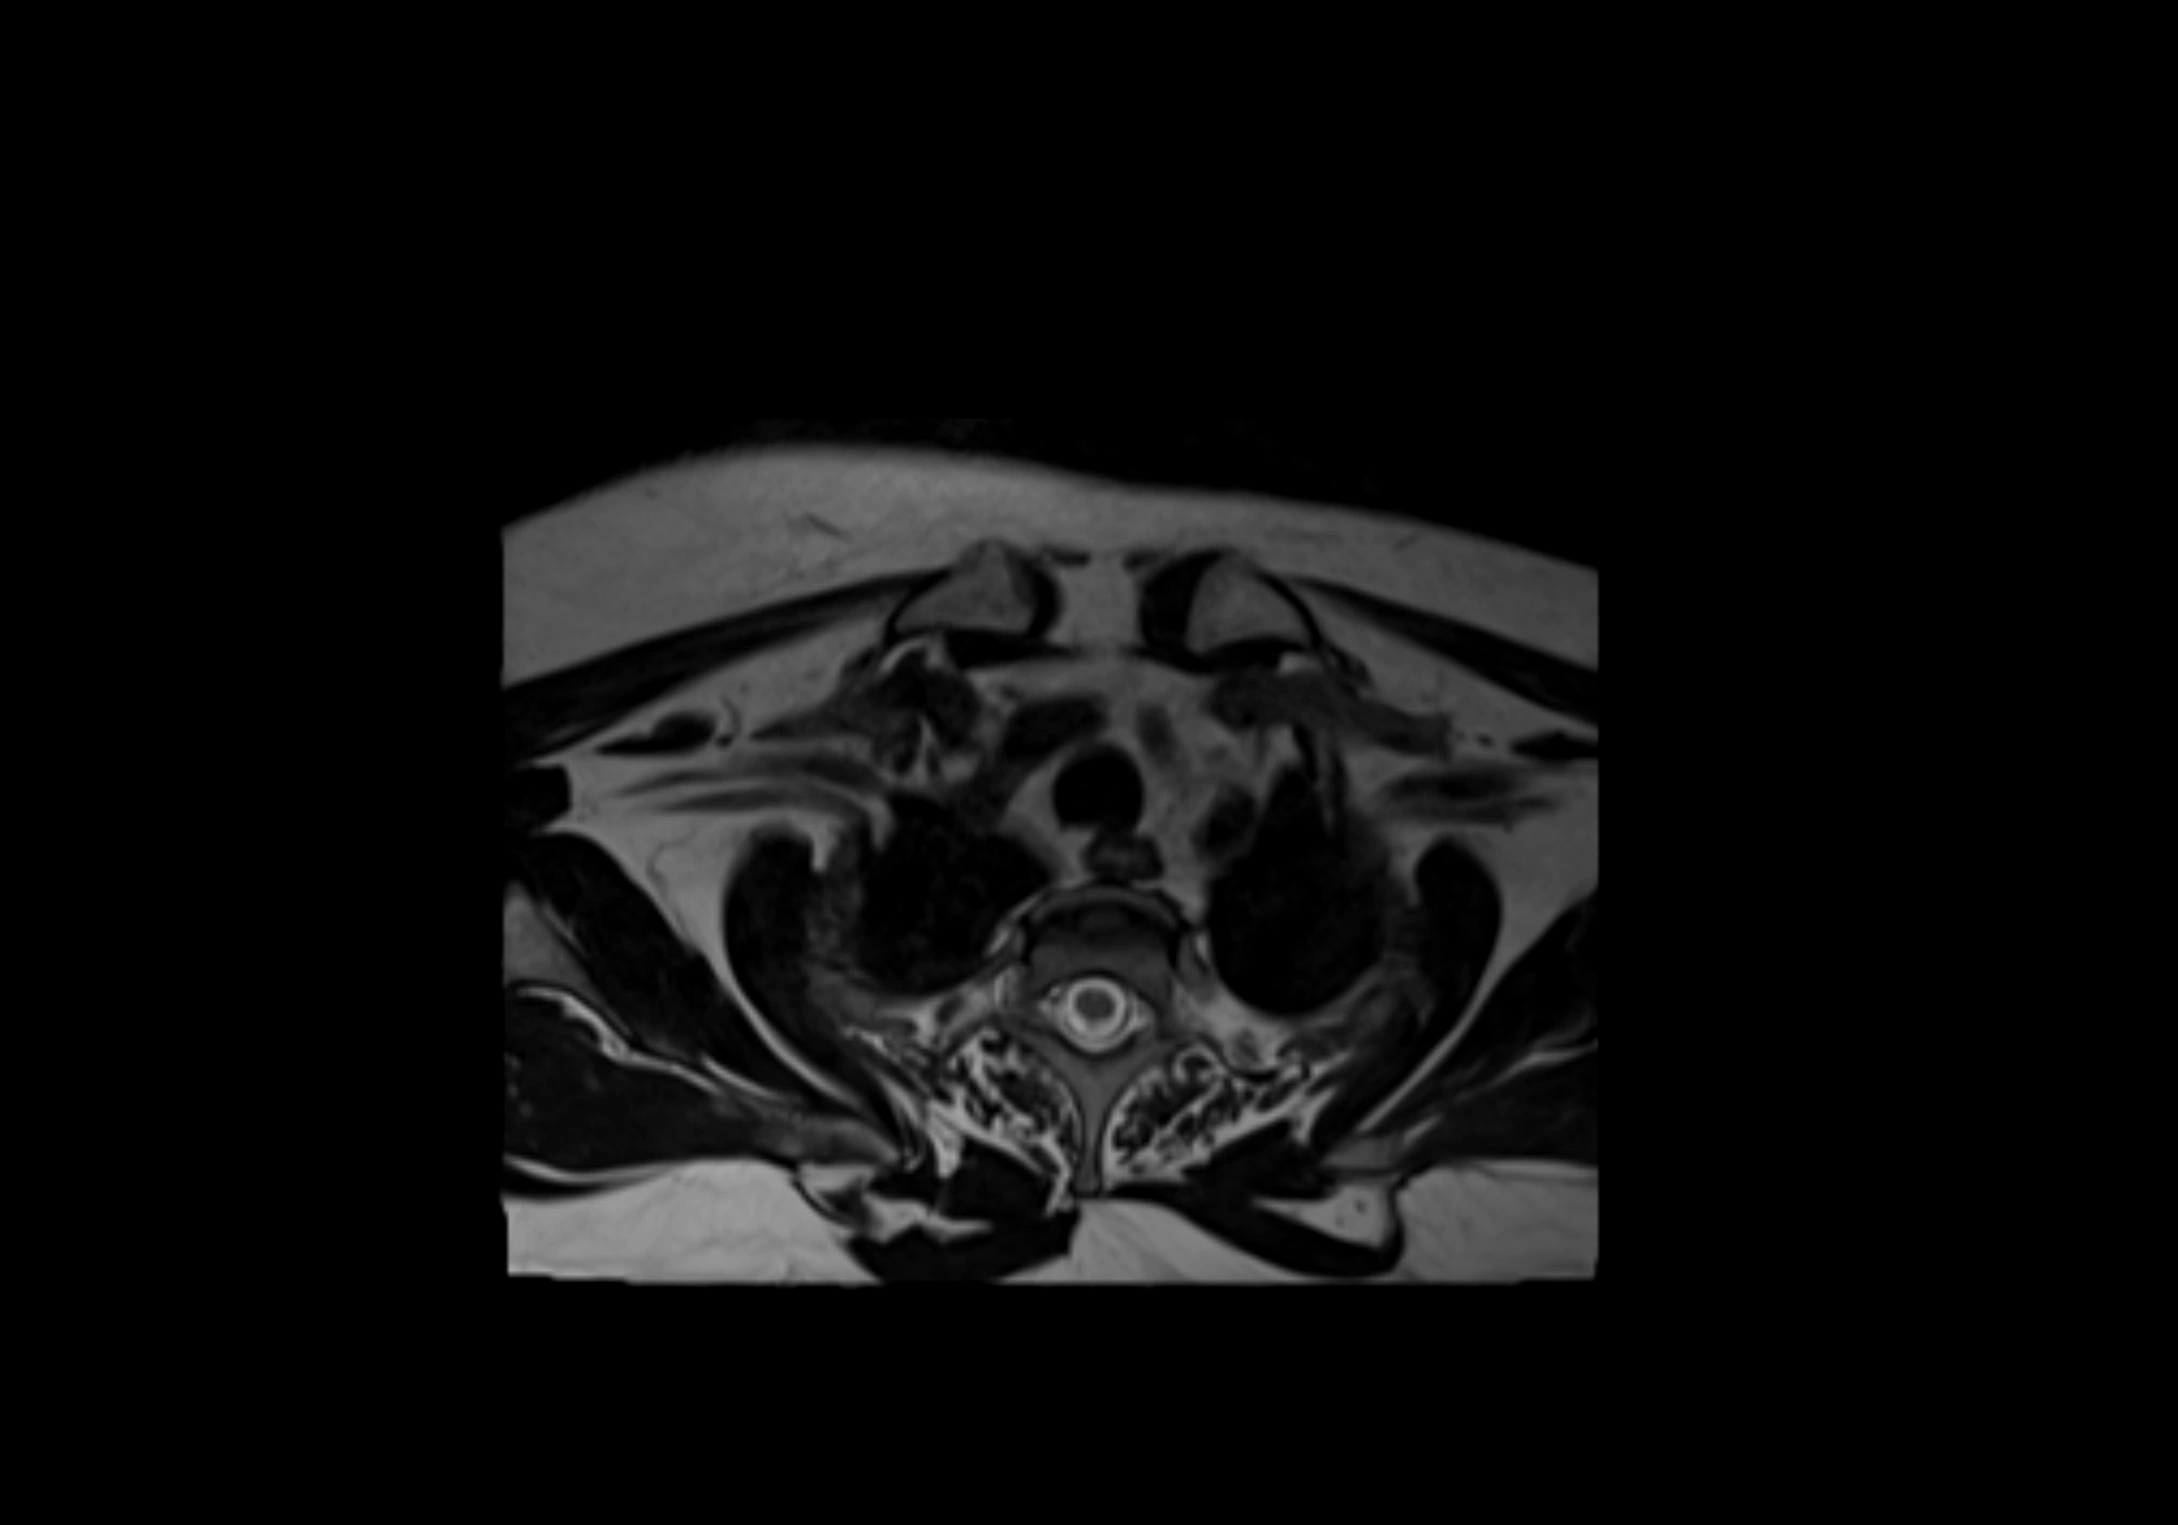

MRI Appearance

T2-weighted images:

• Nodes show intermediate signal, with surrounding fat bright

• Useful for detecting edema, inflammation, or infiltration

• Fatty hilum may appear slightly hyperintense relative to cortex

MRI images

image